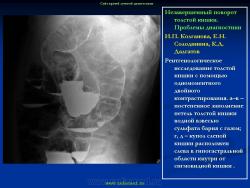

Варианты и аномалии развития толстой кишки.